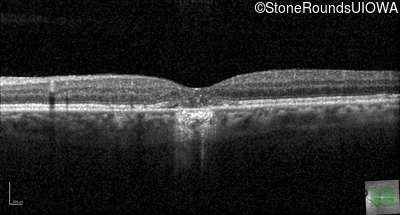

Optical Coherence Tomography - Right - 20/20 +2

Exemplar / OCT Stack